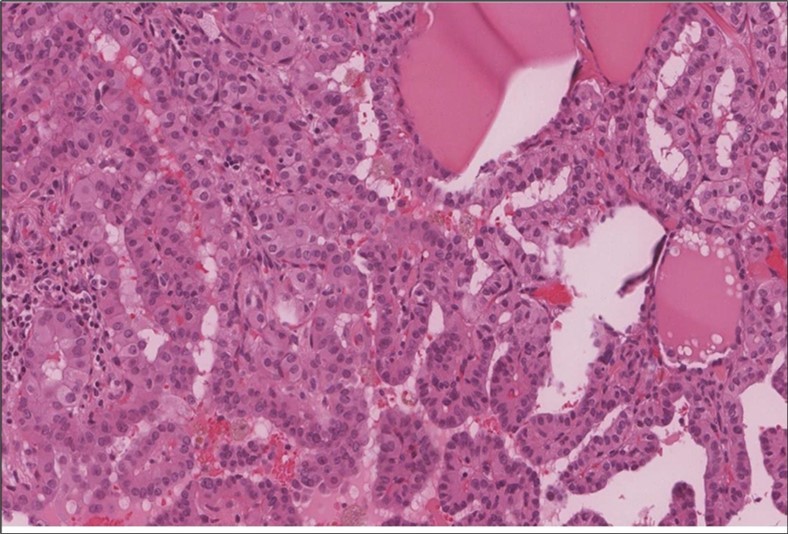

When diagnosing thyroid swelling, imaging studies have been helpful in differentiating malignant from benign tumors with US being used as an initial evaluation tool when assessing thyroid nodules. Tumors are categorized based on composition, echogenicity, shape, margin and echogenic foci into added scores determined by the TI-RADS system, which determines the need for FNA 13. Other imaging modalities include MRI and CT. However; radiological assessment does not distinguish between the types of thyroid cancer, and therefore FNA and biopsy are of crucial importance 3, 6. On a pathologic sample, LMS appears as spindled eosinophilic cells with elongated blunt-ended or cigar-like nuclei arranged in fascicles 2, 7 (Figure 1, Figure 2, Figure 3). Despite the unique microscopic morphology, LMS cannot be distinguished from other spindle cell tumors such as spindle cell variant of medullary thyroid cancer, anaplastic thyroid

Figure 2.Left thyroid On a Higher power, few thyroid follicles are noted and the lesion is composed of spindle cells with sweeping fascicles (H&E, ×200).

Figure 3.Left thyroid The malignant looking cells are showing diffuse atypia, mitosis and hyper-chromatic nuclei, some remaining follicles could be noted as well (H&E, ×400).

cancer, or other metastatic tumors without further testing with genetic or molecular studies 3, 7. Immunohistochemical testing plays a vital role in differentiating LMS from such similar tumors as it stains positive for vimentin and smooth muscle actin (SMA), and is variably positive for HHF35, desmin (50%-100%), and H-caldesmon 3, 6. Moreover, there were no reported cases where thyroid LMS stained positive for thyroglobulin, cytokeratin, calcitonin, chromogranin, or protein S100 3. Our patient’s left thyroid biopsy showed the characteristic microscopic features and was positive for SMA, desmin, caldesmon, P63 with patchy EMA (Figure 1, Figure 2, Figure 3, Figure 4) as well as her liver biopsy (Figure 5, Figure 6, Figure 7); whereas her right thyroid showed clear papillary thyroid cancer cell features (Figure 8, Figure 9).